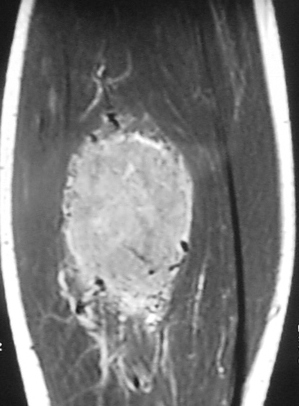

66B) Coronal T1 MRI Of Lower Leg Alveolar Soft Parts Sarcoma

Radiographic imaging is used to help form a diagnosis. These include MRI, CT and Bone Scans

An example of an MRI is shown.